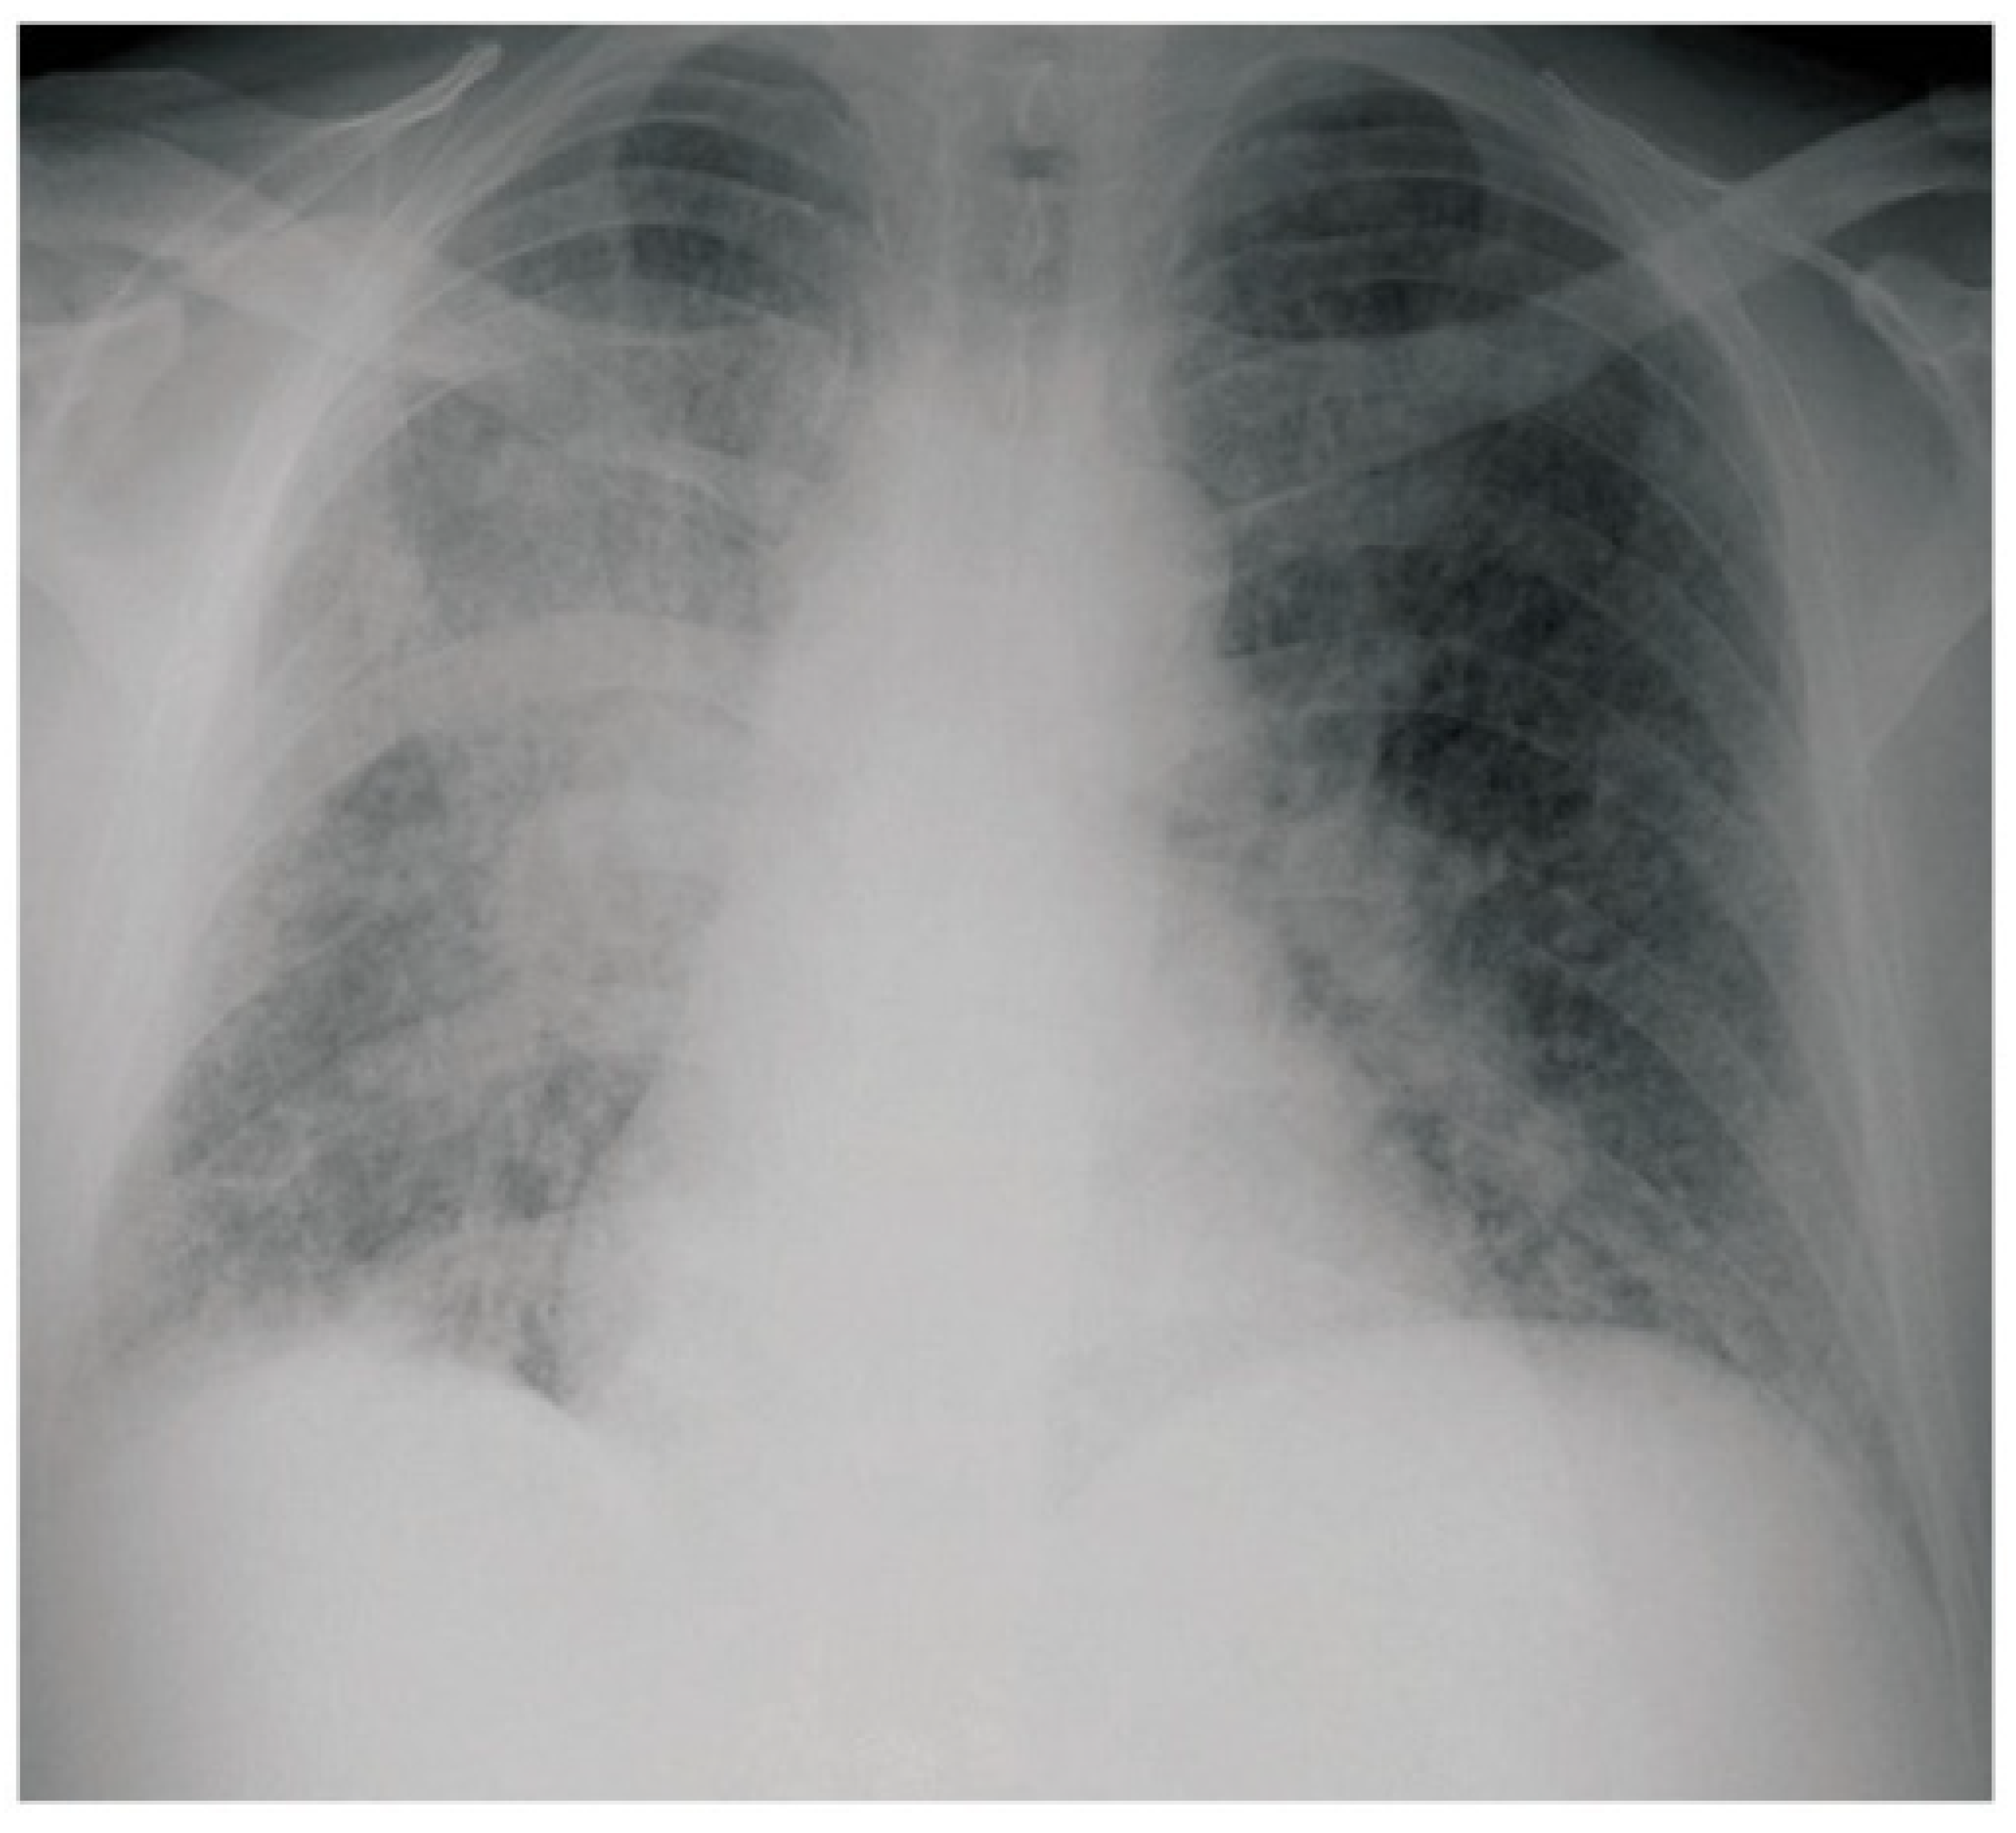

- Maini, R.; Ranjha, S.; Tandan, N.; Regmi, M.R.; Ullah, S.; Stone, T.; Nayeemuddin, F.; Pervin, N. Pulmonary Blastomycosis: A case series and review of unique radiological findings. Med. Mycol. Case Rep. 2020, 28, 49–54. [Google Scholar] [CrossRef]

- Brown, L.R.; Swensen, S.J.; Van Scoy, R.E.; Prakash, U.B.; Coles, D.T.; Colby, T.V. Roentgenologic Features of Pulmonary Blastomycosis. Mayo Clin. Proc. 1991, 66, 29–38. [Google Scholar] [CrossRef]